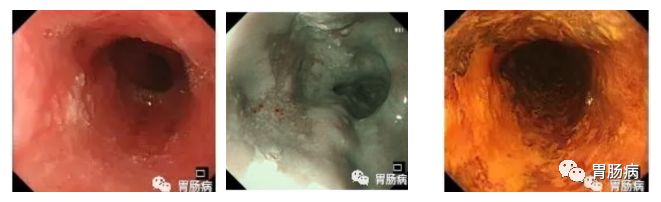

上图.普通胃镜检查,未使用消泡剂影响检查视野

2、与普通胃镜相比,术前准备更充分。普通胃镜检查,虽然患者是空腹状态,但胃肠道内有较多粘液及泡沫不能完全消除,影响内镜下观察效果。

胃镜精查检查前15-30分钟,给予患者黏液溶解剂及祛泡剂以完全清除上消化道内黏液与气泡,有效改善视野清晰度,大大提高微小病变的检出率,见图1。

图1a 去除黏液及泡沫前1b除黏液及泡沫后(右)